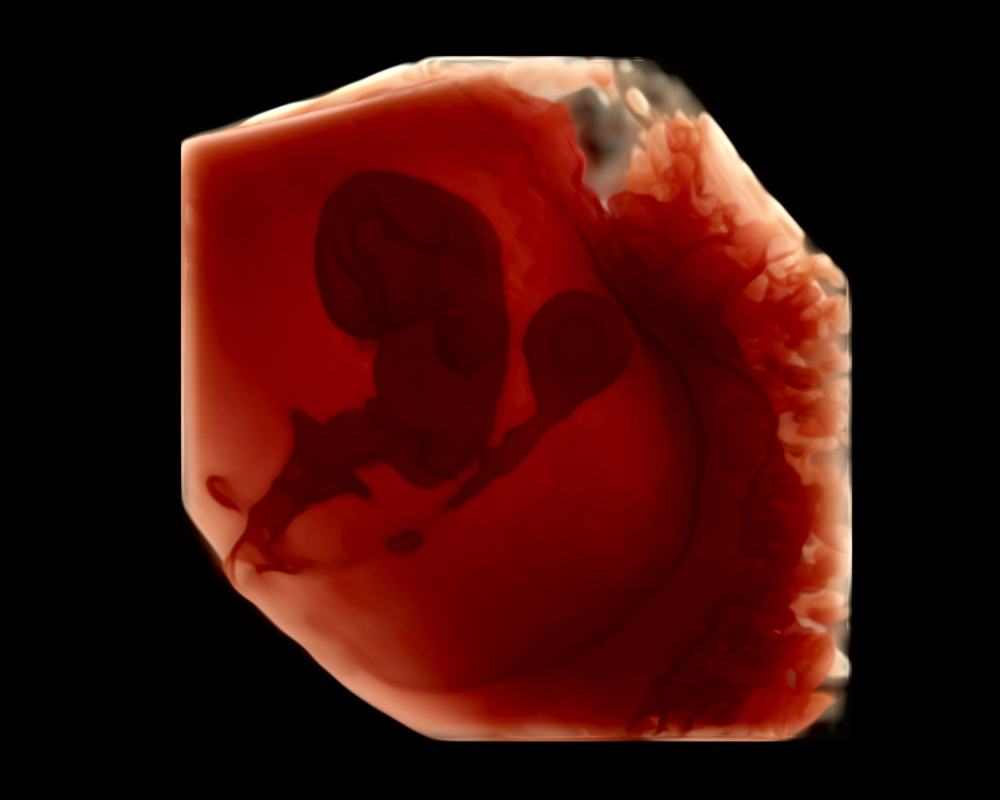

Eco Anatómico 4D

Realizado entre las semanas 20 y 30, el Eco Anatómico 4D, es un estudio que permite una valoración detallada del crecimiento, órganos y estructuras de bebé. Este eco es crucial para la detección temprana de malformaciones congénitas. Si la posición de bebé y las condiciones nos permiten, podemos llevarnos un hermoso recuerdo al tomar fotografías en 4d.